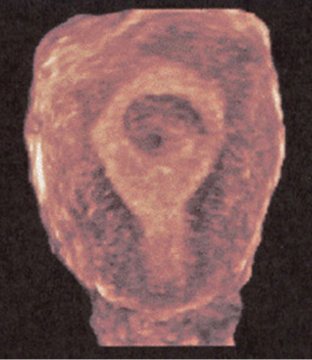

Three-dimensional sonography has many clinical applications in gynecologic disorders (Figs. 8–28 through 8–37). As in obstetrical 3D, gynecologic 3D affords depiction of the uterus and ovaries in any selectable scan plane, including those not readily obtained with 2D. These include improved depiction of endometrial masses such as polyps or submucosal fibroids, improved localization and calculation of changes in fibroid volume, enhanced depiction of tubal masses, intrauterine device localization, and uterine malformations. Three-dimensional depiction of tumor morphology and vascularity within ovarian masses has important implications in distinguishing benign from malignant masses.

FIGURE 8–28. Normal endometrium as shown in coronal plane 3D. (Courtesy of Philips Healthcare.)

Three-dimensional sonography affords depiction of the configuration of the uterine fundus. With a septated uterus, the fundal contour is smooth, whereas with bicornuate and didelphys, a sharp cleft is seen.

Because of its ability to display in the coronal plane, 3D sonography is accurate in depicting intraluminal masses such as polyps or fibroids. The location of an intrauterine contraceptive device (IUCD) within the endometrium is readily depicted with 3D sonography. Three-dimensional sonography obtained in the transverse plane of the uterus fundus is also useful in identifying tubal masses since their origins can be traced to the cornual area of the uterus.